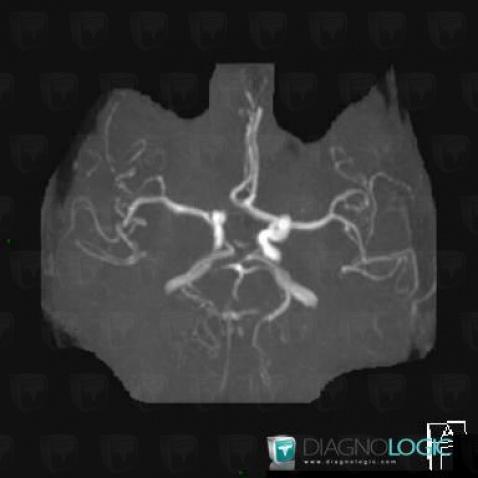

Variante de-normale, Polygone-Willis, IRM

Voici les informations spécifiques à l'image clé ci dessus:

- Diagnostic Variante de la normale, Localisation(s) Polygone de Willis, comportant les gammes